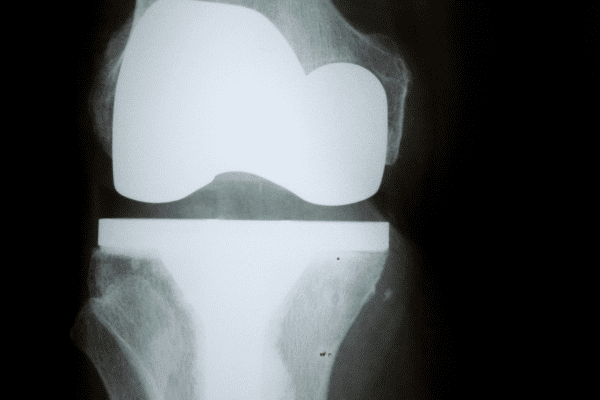

たとえば「人工関節置換術」は、損傷した関節を人工関節に入れ替える手術です。変形性膝関節症が進行し、日常生活に支障が出るほど痛みが強い場合に検討されます。手術により痛みを軽減し、関節の機能回復を図ります。